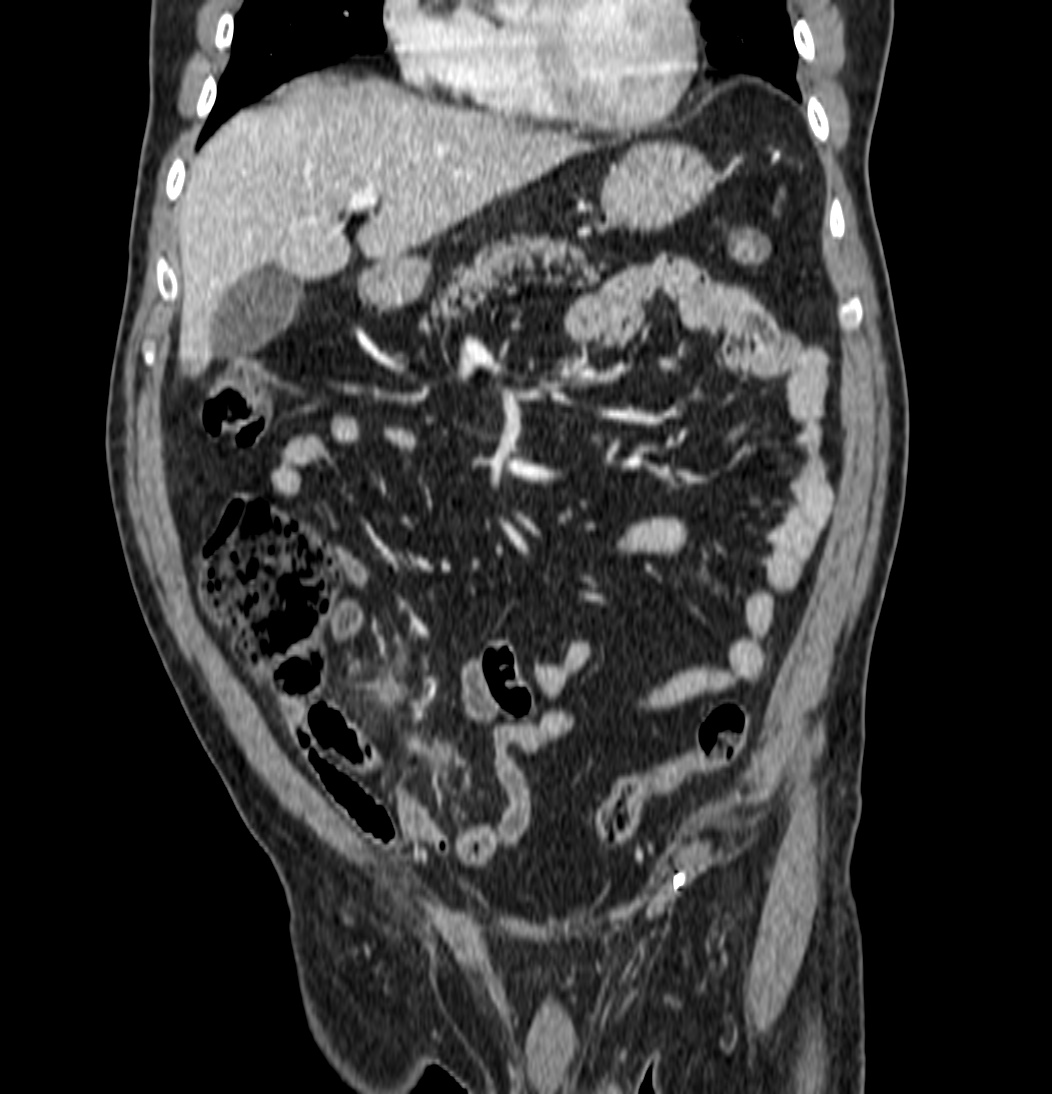

Ante la persistencia del dolor, el elevado IMC del paciente y la necesidad de descartar patología de FID, apendicitis, se decidió realizar TAC de abdomen:

Nos enfrentamos a un poceso que afecta el Epiplon, más concramente un apéndice (o colgajo) del mismo, compuesto por grasa y vasos que se inflaman por compromiso vascular venoso. Se denomina Apendagitis y lo podemos confudir, entre otras entidades, con una apendicitis.

Se sospecha diverticulitis, se realiza TAC de abdomen:

Al igual que el caso anterior, nos encontramos nuevamente ante una apendagitis. Esta vez la sospecha era por diverticulitis, la anterior creíamos enfrentarnos a una apendicitis probablemente.

TAC: Imagen oval con aumento de la atenuación central, inferior a 5 cm de diámetro, contigüa al colon, con afectación de la grasa periférica. El aumento de la atenuación central es un signo de trombosis venosa muy útil para el diagnóstico, pero su ausencia no excluye en diagnóstico de apendagitis. Otros hallazgos, como aumento de la pared colónica o formación de abscesos son raros. Aunque los síntomas remiten en dos semanas, los cambios en la TAC pueden prolongarse más tiempo (pueden mantenerse, disminuir o quedar una atenuación residual), aunque en 6 mese suele haber remitido completamente. En Ecografía suele observarse en el área de máxima sensibilidad al dolor, una masa hiperecogénica, inferior a 5 cm, no compresible, adyacente al colon y sin señal Doppler.